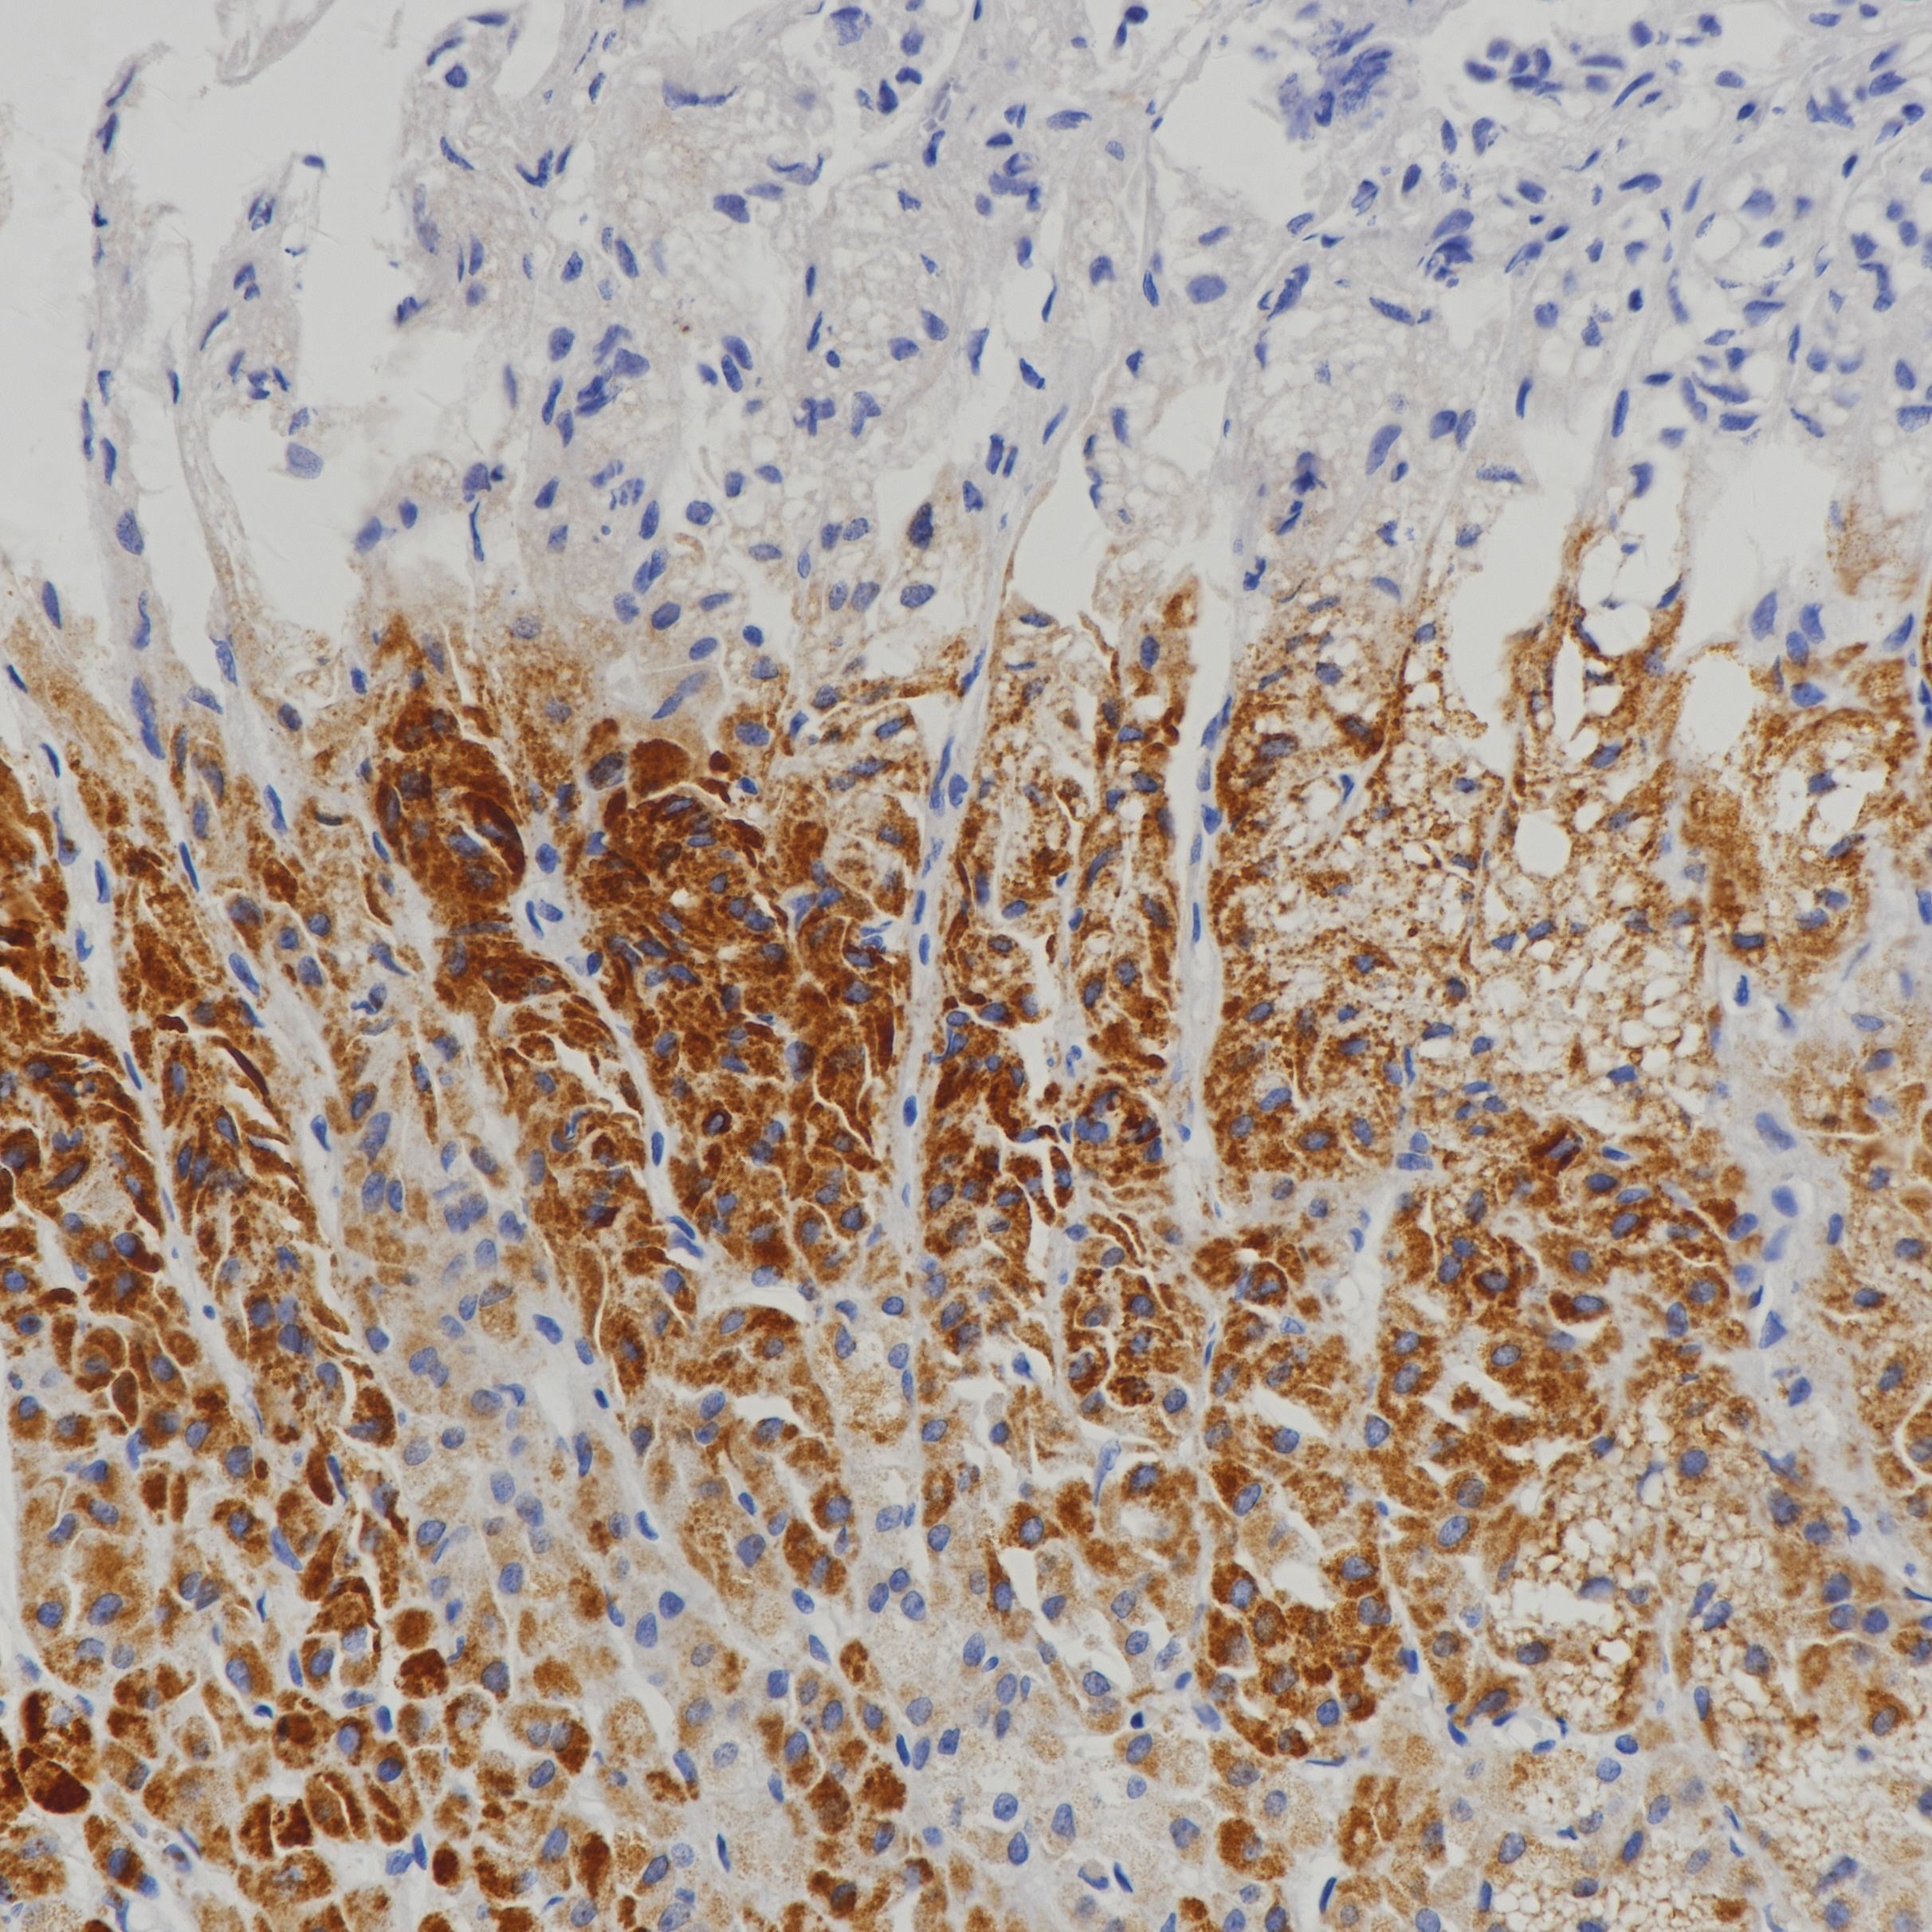

2.苏婷婷. 神经内分泌肿瘤PAX-5、FHIT表达与临床和病理类型关联性研究[D].广西医科大学,2019.